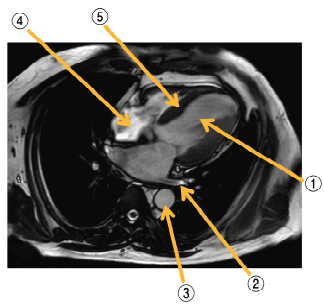

18 正常な成人男性の胸部 MRI別冊No. 1 を別に示す。 図に示す部位と名称の組合せで誤っているのはどれか。 (A)① 左心室 (B) ② 肺動脈 (C) ③ 下行大動脈 (D) ④ 右心房 (E) ⑤ 心室中隔